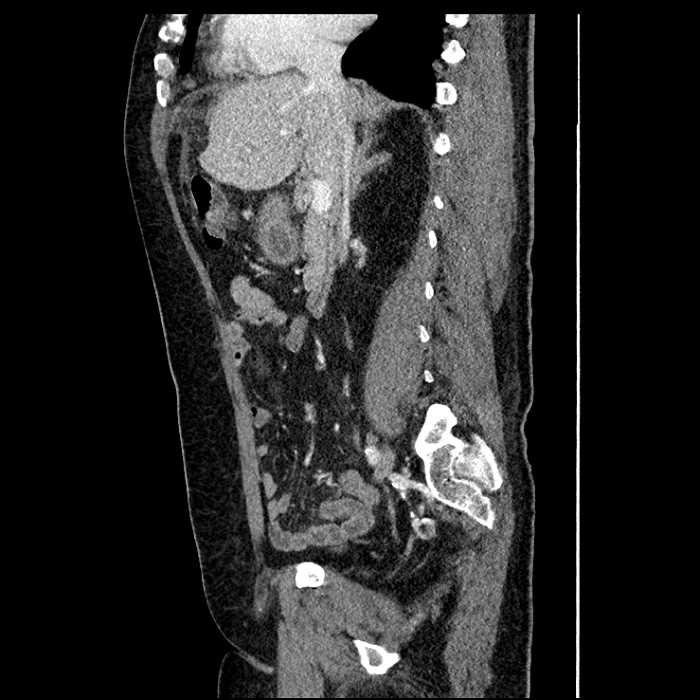

Age: 63

Sex: Male

Indication: Abdominal pain

• Mild mural thickening of a segment of the sigmoid colon with adjacent fat stranding and a 1.5 cm fluid and gas collection along the tip of an inflamed diverticulum

• Loss of the normal fat plane between this collection and adjacent loops of small bowel, which demonstrate mural thickening

• No bowel obstruction

• High grade stenosis of the left common iliac artery, with the left internal and external iliac arteries remaining patent

Acute sigmoid diverticulitis complicated by a small contained perforation and a large abscess in the right hepatic lobe. Additional small subcapsular abscesses along the anterior margin of the left hepatic lobe.

Additionally, loss of the normal fat plane between the peridiverticular collection and adjacent thickened loops of small bowel raises the potential for an enterocolonic fistula.

High grade stenosis of the left common iliac artery. The left external and internal iliac arteries are patent.

Hepatic abscess showing the double target sign with low density internally surrounded by a thin inner enhancing rim (red arrow) and ill-defined outer low density rim (yellow arrow). Blue arrow indicates an internal septation. Red arrows: additional smaller subcapsular abscesses. Red arrow: focal contained perforation associated with diverticulitis.